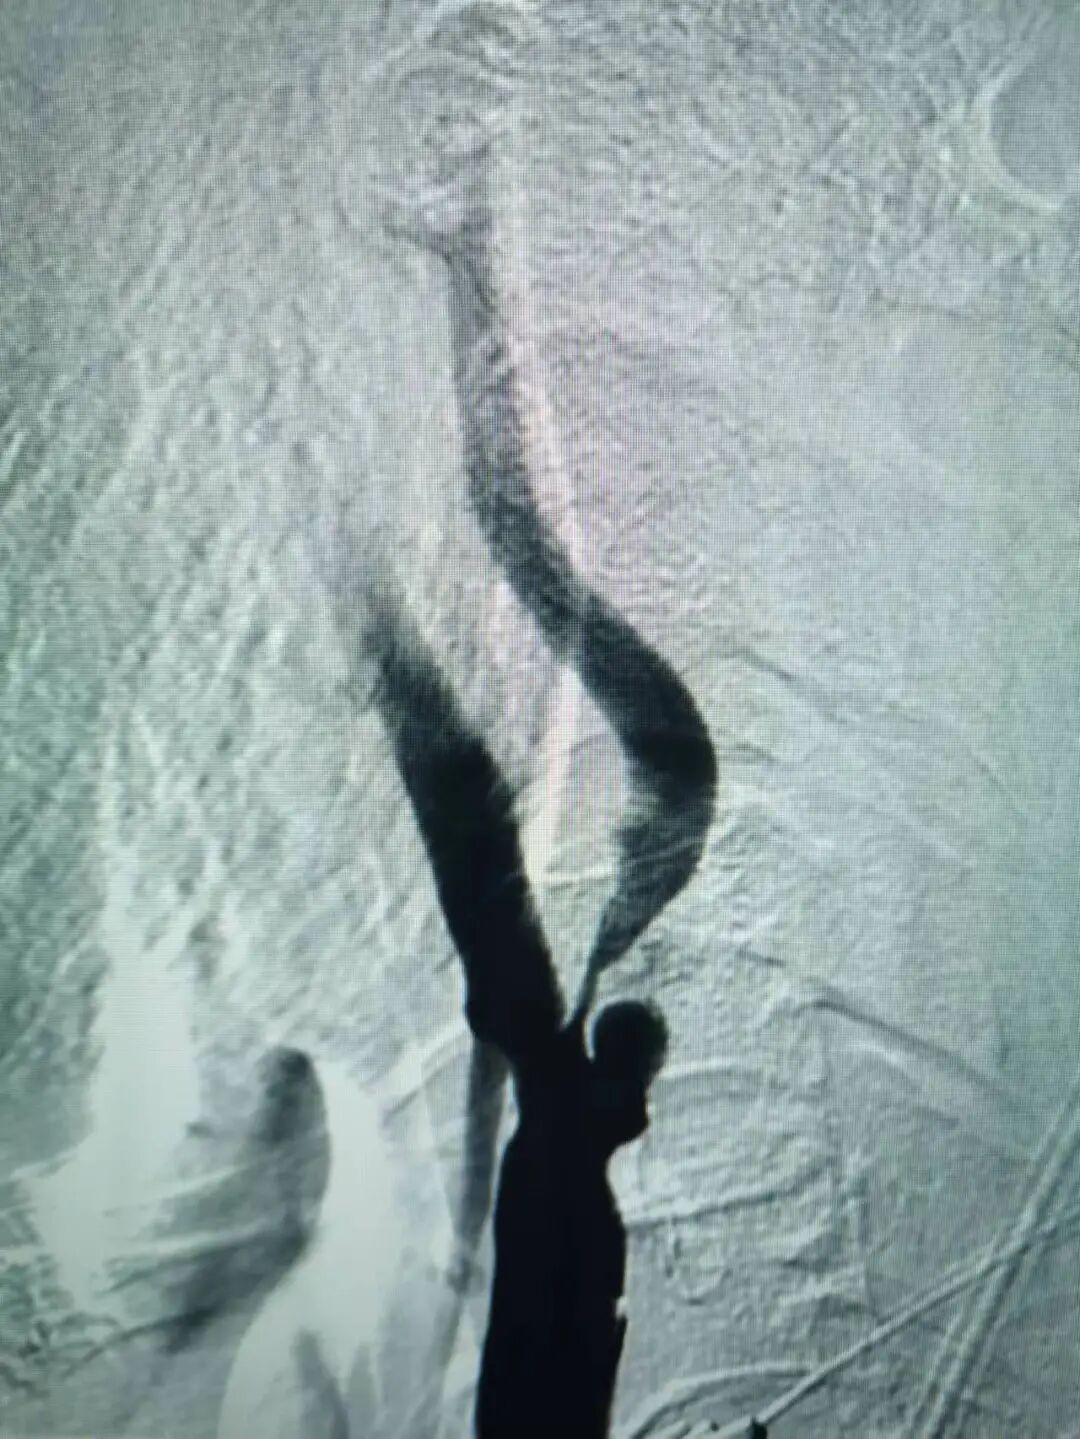

術后造影